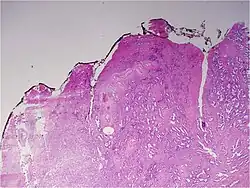

![]() Gleason grade — Lower grades are associated with small, closely packed glands. Cells spread out and lose glandular architecture as grade increases. Gleason score is calculated from grade as described in the text. |